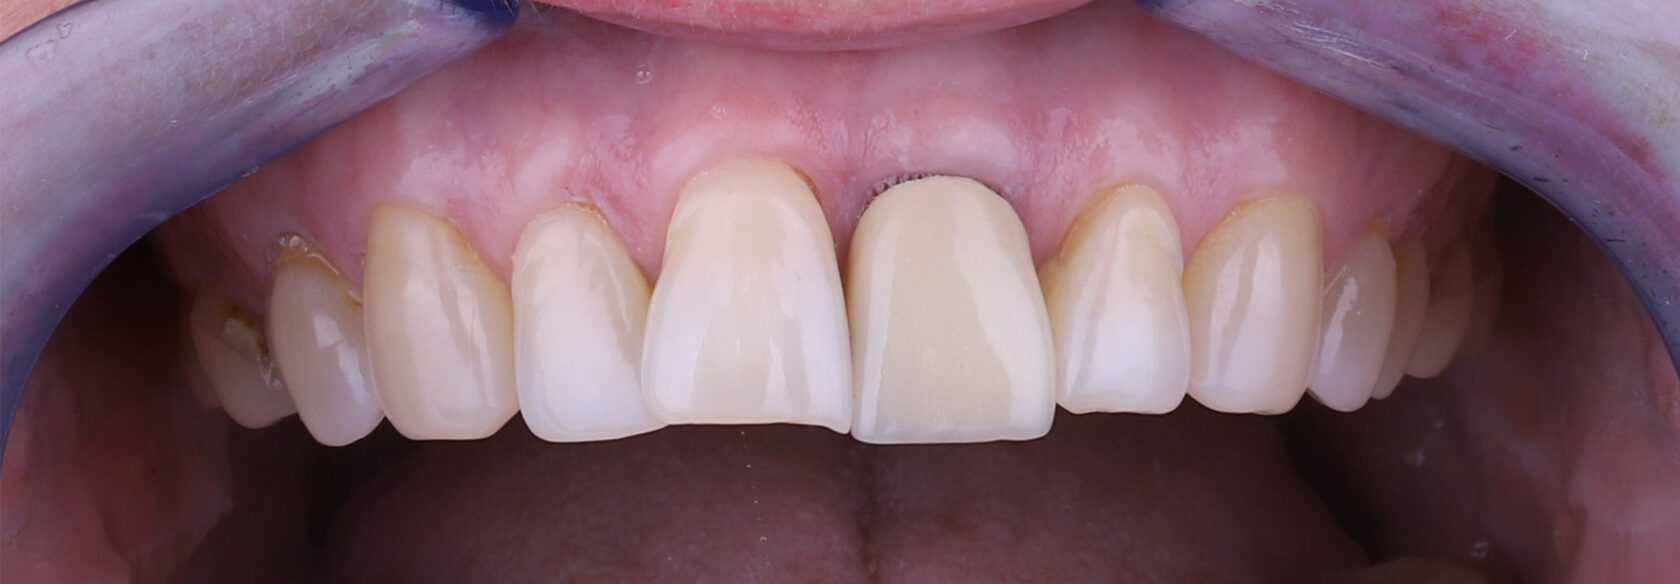

Эстетическое протезирование передней группы зубов коронкой E-max и композитной реставрацией